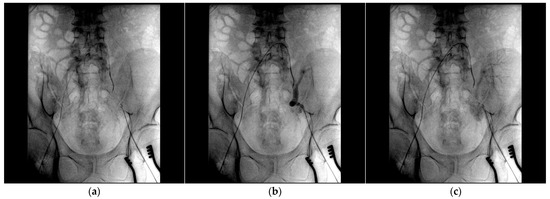

2. Case Report